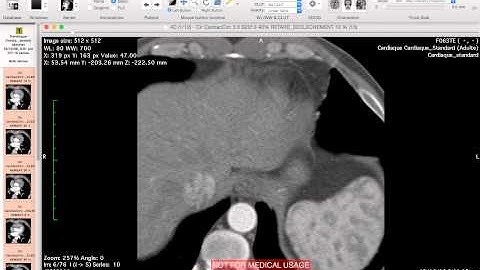

EVAR Planning - Proximal neck assessment - How i do it with Osirix